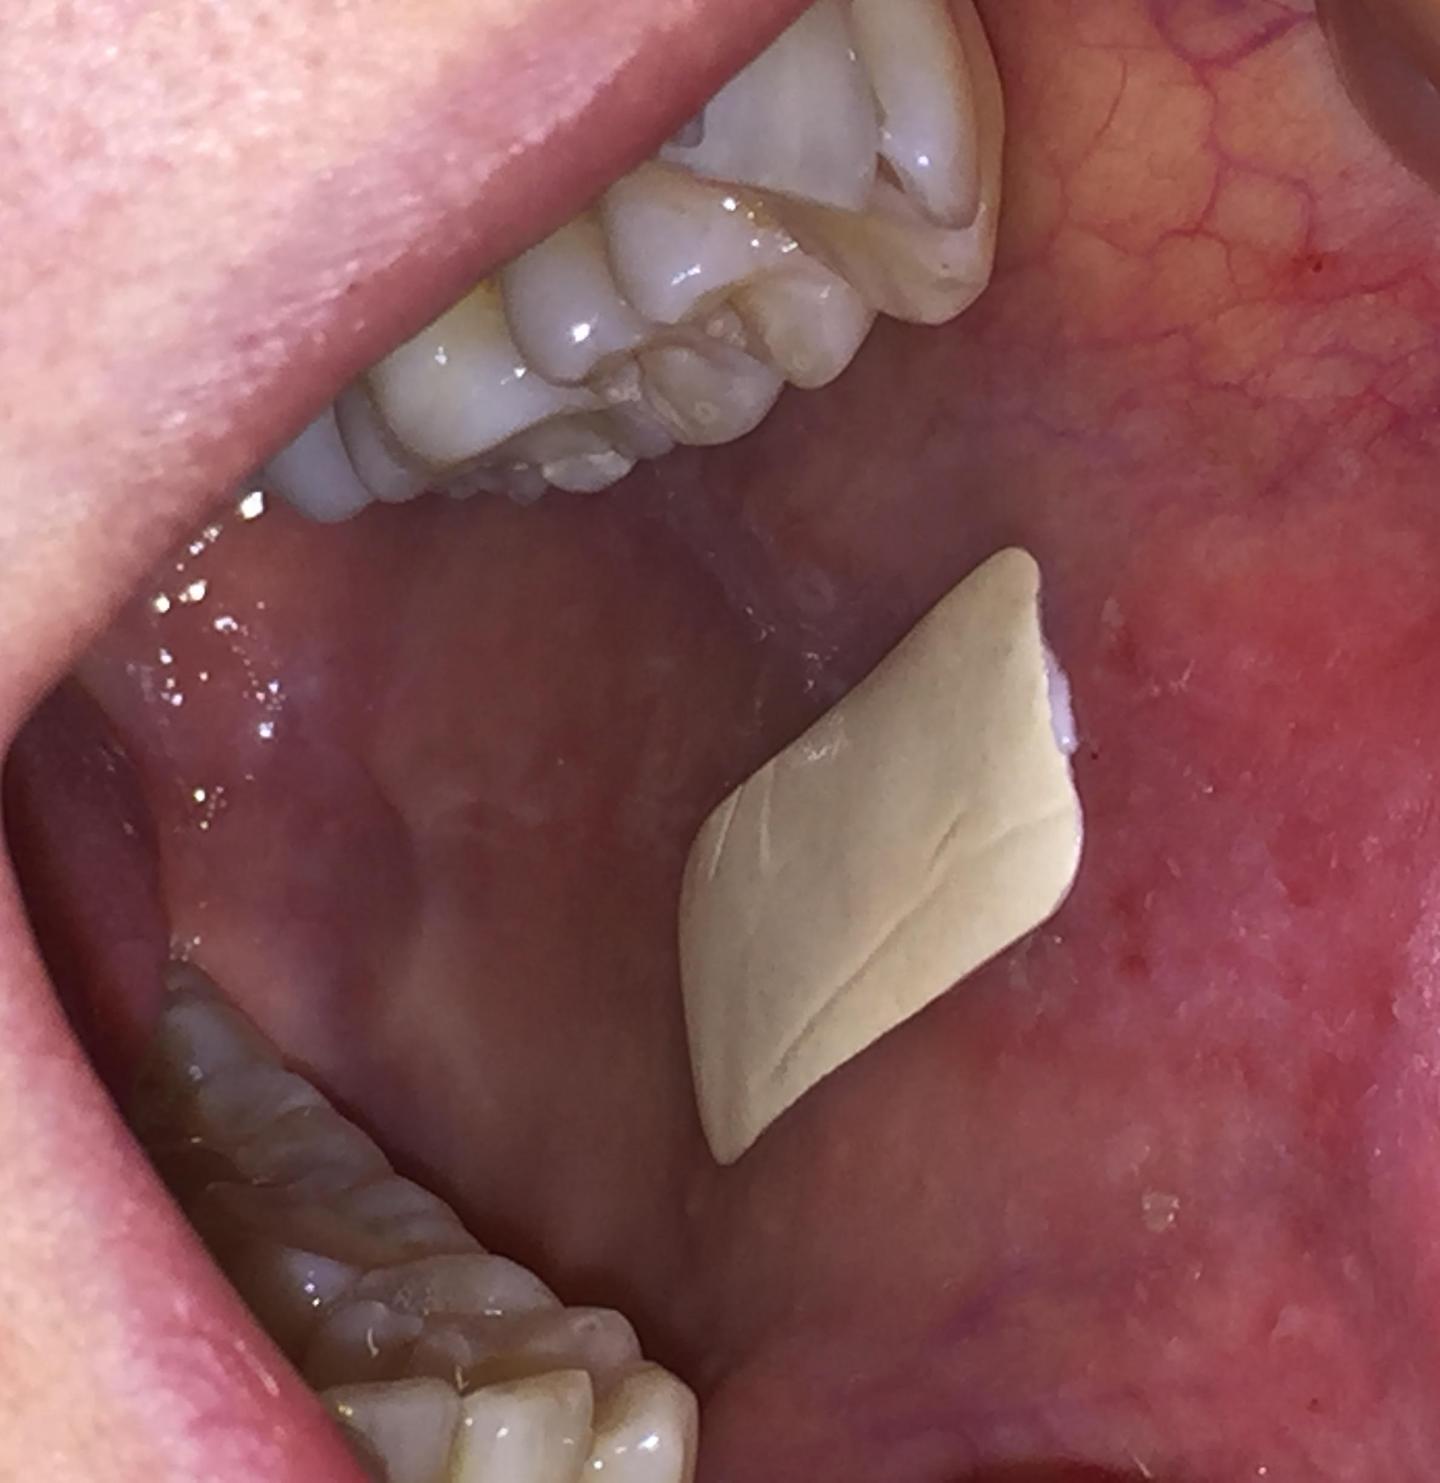

Patches In A Mouth . Leukoplakia is a white patch or patches in the mouth. The patches can be flat or they may appear nodular or elevated. Pvl may look like small white patches in your mouth. Mild leukoplakia is usually harmless and often goes away on its own, but it may be a sign of a more serious condition. If you have a white patch in your mouth that does not go away, get it checked by a dentist or gp. Trying to wipe off the white patches. Or the condition may be a sign of oral. These qualities indicate that leukoplakia is more likely to become cancerous than the homogenous type. These patches can appear uniform in color. Leukoplakia is a condition involving white patches that form inside the mouth. Leukoplakia, or white and gray patches inside the mouth, may be caused by irritation. The white spots in the mouth caused by leukoplakia could become cancerous. White patches in your mouth are a sign of leukoplakia. The patches can grow on your tongue, gums, the soft tissue between your lips and. Talking about your medical history and risk.

These qualities indicate that leukoplakia is more likely to become cancerous than the homogenous type. Leukoplakia is a condition involving white patches that form inside the mouth. If you have a white patch in your mouth that does not go away, get it checked by a dentist or gp. Trying to wipe off the white patches. Talking about your medical history and risk. Leukoplakia is a white patch or patches in the mouth. Mild leukoplakia is usually harmless and often goes away on its own, but it may be a sign of a more serious condition. The patches can be flat or they may appear nodular or elevated. Looking at the patches in your mouth. The white spots in the mouth caused by leukoplakia could become cancerous.

Patches In A Mouth Or the condition may be a sign of oral. White patches in your mouth are a sign of leukoplakia. The white spots in the mouth caused by leukoplakia could become cancerous. The patches can grow on your tongue, gums, the soft tissue between your lips and. Looking at the patches in your mouth. The patches can be flat or they may appear nodular or elevated. These qualities indicate that leukoplakia is more likely to become cancerous than the homogenous type. These patches can appear uniform in color. Leukoplakia is a white patch or patches in the mouth. Mild leukoplakia is usually harmless and often goes away on its own, but it may be a sign of a more serious condition. Trying to wipe off the white patches. Or the condition may be a sign of oral. Leukoplakia is a condition involving white patches that form inside the mouth. Talking about your medical history and risk. If you have a white patch in your mouth that does not go away, get it checked by a dentist or gp. Leukoplakia, or white and gray patches inside the mouth, may be caused by irritation.